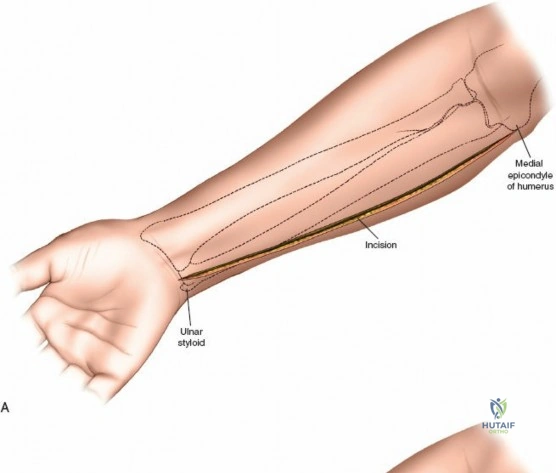

Accurate identification of surface landmarks is the first step in a successful Henry approach. Palpate the biceps tendon, a stout, taut structure crossing the anterior elbow joint just medial to the brachioradialis muscle. Next, palpate the brachioradialis itself, the fleshy muscle forming the lateral border of the cubital fossa. Finally, identify the styloid process of the radius distally. Note that when the forearm is fully supinated (the anatomic position), the radial styloid is truly lateral.

Make a straight or gently curved incision beginning at the anterior flexor crease of the elbow, just lateral to the biceps tendon. Extend this incision distally toward the styloid process of the radius. The exact length and placement of the incision are dictated by the specific pathology; the approach is highly modular, and often only the proximal, middle, or distal third of the incision is required.

Superficial Surgical Dissection and Internervous Plane

Incise the deep fascia of the forearm in line with the skin incision. The initial goal is to identify the medial border of the brachioradialis as it courses down the forearm. It is a common pitfall to search for this border too far laterally. At the level of the elbow, the brachioradialis is expansive and extends almost halfway across the anterior forearm. It is surprisingly easy to mistake the plane between the brachioradialis and the extensor carpi radialis longus for the correct intermuscular plane.

To confirm the correct plane, look for the superficial branch of the radial nerve. This sensory nerve runs on the undersurface of the brachioradialis muscle. Once the true medial edge of the brachioradialis is found, develop the plane between it and the pronator teres (proximally) or the flexor carpi radialis (distally). Retract the brachioradialis laterally, taking care to keep the superficial radial nerve attached to its undersurface to protect it from traction injury.